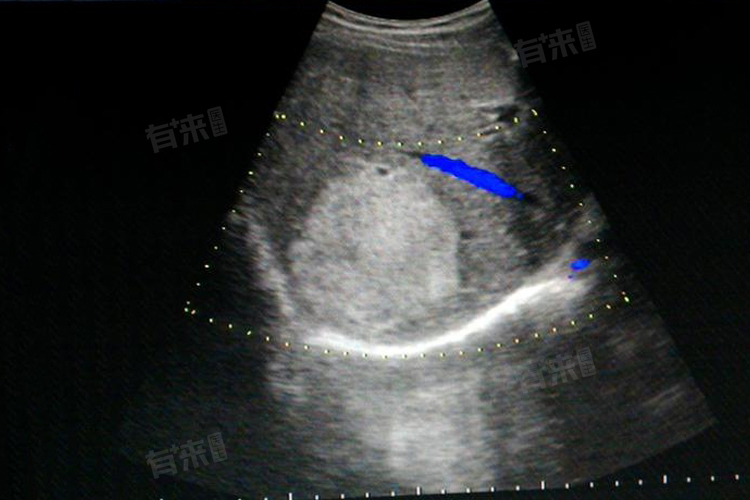

肝血管瘤8mmx7mm通常不严重,属于肝脏的良性肿瘤,生长缓慢且无恶变倾向,目前体积较小,无需特殊治疗,但需定期随访观察。

- 肝血管瘤是肝脏内的一种常见良性肿瘤,以肝海绵状血管瘤最为多见,发生可能与先天性发育异常、激素刺激、感染等因素有关。该肿瘤一般生长缓慢,且无明显恶变倾向,在体积较小时,如8mmx7mm,通常不会对患者的身体健康造成显著影响。患者往往无明显临床症状,无需进行特殊治疗,但建议定期到医院进行复查,以便及时了解血管瘤的生长情况。